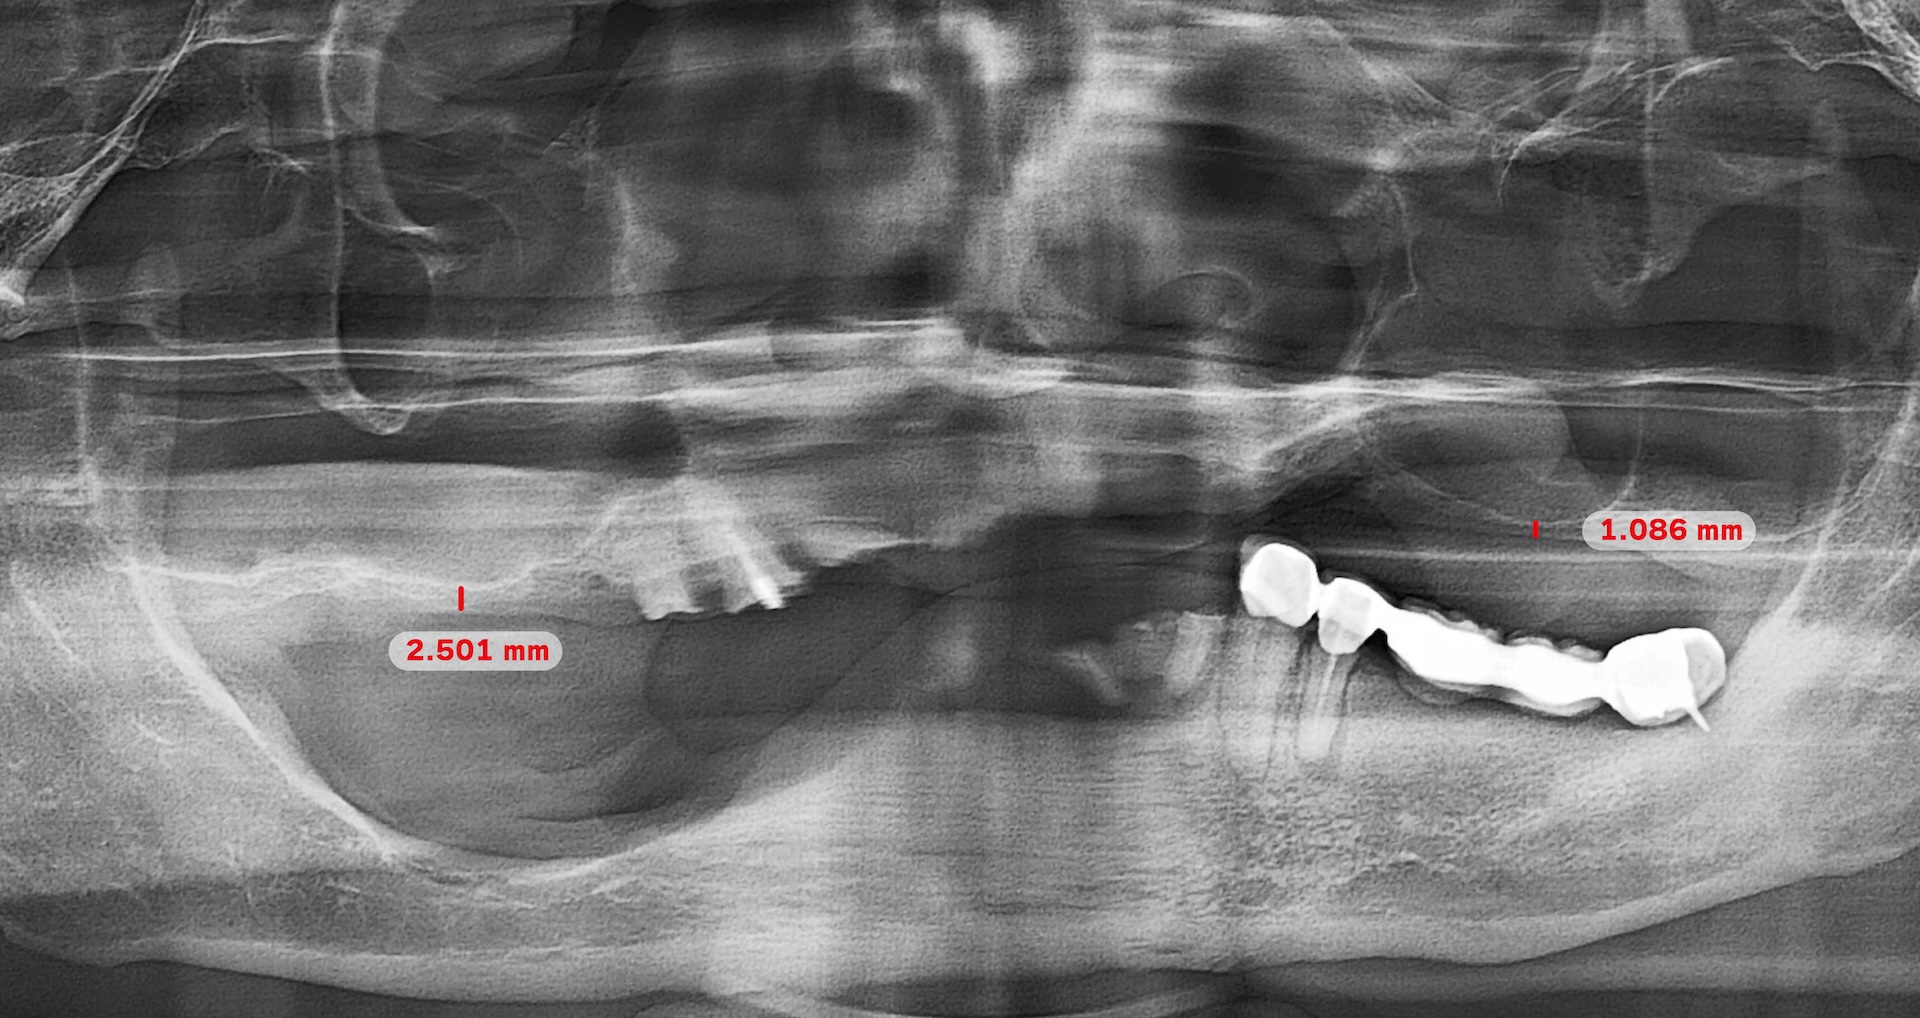

蒔美全口重建中心主任、口腔顎面外科專科賴泓璋醫師透過全頭顱電腦斷層與數位口掃精準評估齒槽骨與牙齦狀態,再深入了解他對咬合、外觀與生活品質的需求。

Dr. Hung-Chang Lai, head of the Full-Mouth Reconstruction Center, used craniofacial CBCT scan and a 3Shape intraoral scanner to assess his condition, then listened closely to his concerns.

賴醫師回憶:「第一次檢查時,莫教授就說想立刻裝上固定假牙。但我坦白告訴他:你的骨頭條件有限,尤其是上顎,骨質薄弱,甚至距離鼻竇不到 3 公釐,因此當天無法立即裝上固定假牙。不過,我們會先為你製作臨時活動假牙,既能維持自然外觀,也提供基本咀嚼功能。」

Dr. Lai recalled, “During our first consultation, Professor Mo told me he wanted to have permanent teeth fitted right away. I had to be honest with him: his bone structure, especially in the upper jaw, was too weak, and the distance to the sinus was less than three millimeters. That made it impossible to place permanent teeth on the day of surgery. Instead, we prepared a temporary set of removable teeth, which would preserve a natural appearance and allow basic chewing function.”